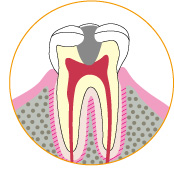

虫歯にかかっている人は、歯医者に行って治療を受けないといけません。通常虫歯になると、虫歯になっている部分を削ることになります。ということは、虫歯を除去した後には、歯に空洞の穴ができているということになるわけです。そのままの状態で放置するというわけにはいきません。

虫歯にかかっている人は、歯医者に行って治療を受けないといけません。通常虫歯になると、虫歯になっている部分を削ることになります。ということは、虫歯を除去した後には、歯に空洞の穴ができているということになるわけです。そのままの状態で放置するというわけにはいきません。

インレーもしくはクラウンというものを使って、虫歯を削った歯のフォローをすることになります。

虫歯にかかっている人は、歯医者に行って治療を受けないといけません。通常虫歯になると、虫歯になっている部分を削ることになります。ということは、虫歯を除去した後には、歯に空洞の穴ができているということになるわけです。そのままの状態で放置するというわけにはいきません。

インレーもしくはクラウンというものを使って、虫歯を削った歯のフォローをすることになります。